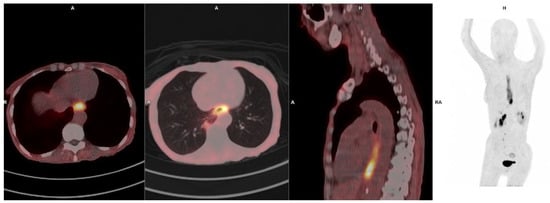

3.8. Esophageal Cancer

- Zhao, L.; Chen, S.; Chen, S.; Pang, Y.; Dai, Y.; Hu, S.; Lin, L.E.; Fu, L.; Sun, L.; Wu, H.; et al. 68Ga-fibroblast activation protein inhibitor PET/CT on gross tumour volume delineation for radiotherapy planning of oesophageal cancer. Radiother. Oncol. 2021, 158, 55–61. [Google Scholar] [PubMed]

- Liu, H.; Yang, X.; You, Z.; Hu, Z.; Chen, Y. Role of 68Ga-FAPI-04 PET/CT in the initial staging of Esophageal Cancer. Nuklearmedizin 2023, 62, 38–44. [Google Scholar] [PubMed]

- Ristau, J.; Giesel, F.L.; Haefner, M.F.; Staudinger, F.; Lindner, T.; Merkel, A.; Schlittenhardt, J.; Kratochwil, C.; Choyke, P.L.; Herfarth, K.; et al. Impact of primary staging with fibroblast activation protein specific enzyme inhibitor (FAPI)-PET/CT on radio-oncologic treatment planning of patients with esophageal cancer. Mol. Imaging Biol. 2020, 22, 1495–1500. [Google Scholar]

- Wegen, S.; Claus, K.; Linde, P.; Rosenbrock, J.; Trommer, M.; Zander, T.; Tuchscherer, A.; Bruns, C.; Schlößer, H.A.; Schröder, W.; et al. Impact of FAPI-46/dual-tracer PET/CT imaging on radiotherapeutic management in esophageal cancer. Radiat. Oncol. 2024, 19, 44. [Google Scholar] [CrossRef]